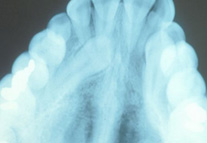

• Dental Implants

Dental Implants